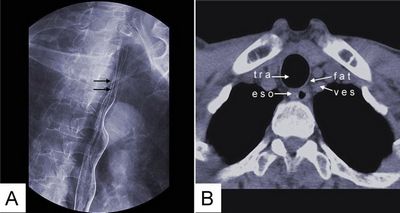

КТ може допомогти виявити захворювання стравоходу кількома способами. По-перше, КТ може виявити аномалії в стравоході, такі як пухлини, стриктури (звуження) або запалення. Зображення, отримані за допомогою КТ, можуть також показати, чи поширилася пухлина на сусідні лімфатичні вузли або органи, що може допомогти лікарям визначити стадію раку. Крім того, КТ може виявити інші захворювання, які можуть бути причиною симптомів пацієнта, такі як грижа стравохідного отвору діафрагми або виразка.

На закінчення, КТ є цінним інструментом для виявлення захворювань стравоходу. Створюючи детальні зображення внутрішньої частини тіла, вона може допомогти лікарям виявити аномалії в стравоході та навколишніх тканинах. Пацієнти, які проходять КТ, повинні знати про підготовку, необхідну для проведення дослідження, а також про потенційні ризики та ускладнення, пов'язані з ним. Тісно співпрацюючи зі своєю медичною командою, пацієнти можуть гарантувати, що вони отримають найточніший діагноз і відповідне лікування для свого стану.